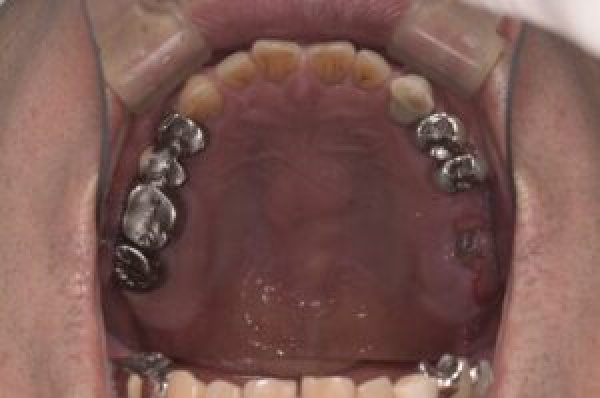

| 備考 | 右上の欠損部へのインプラントを希望で来院されました。 左下のブリッジの下にものが挟まりやすいとのことでブリッジ部分もインプラント埋入を希望されました。口腔内の銀歯も全て綺麗にやりかえたいとのことで、ダイレクトボンディングやセラミックインレーやジルコニアクラウンでやりかえていきました。 右上6番のインプラント埋入時にはソケットリフトで骨造成を行なっています。 見た目だけではなく噛みやすくなりとても満足されています。現在はエアフローのクリーニングやホワイトニングで通院されています。 |